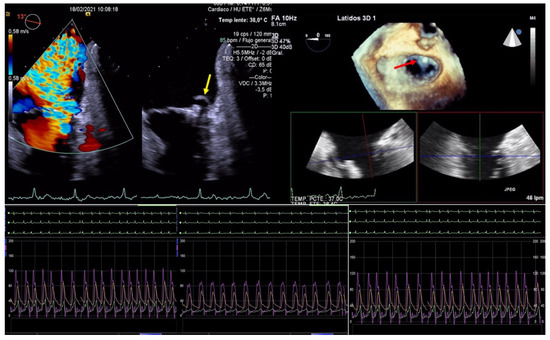

TEE allows for the assessment of the ASD, morphology, and size, it being superior to visualization through 3D-TEE. If the percutaneous closure of the ASD is necessary, the TEE is essential in guiding the procedure [27] (Figure 7).

Figure 7.

Persistent atrial septal defect. (Left) Three-dimensional transesophageal echocardiogram image showing a large atrial septal defect with tearing of the tissue through the transseptal puncture area (yellow arrow) from the left atrium. (Right): Two-dimensional transesophageal echocardiogram showing an Amplatzer device closing the iatrogenic atrial septal defect (red arrow).